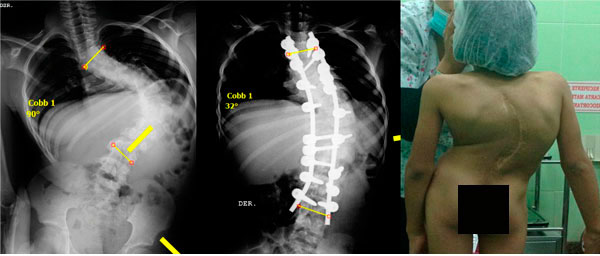

Cifosis rígida toracolumbar (Enfermedad de Scheuermann): varón de 20 años, consulta por dolor toraco lumbar intenso, realizo 4 anos de terapia física y rehabilitación sin éxito. 10 meses Post-operado, se tuvo que realizar varias osteotomías de columna, actualmente sin dolor, realiza actividades cotidianas sin limitaciones.